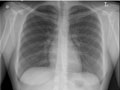

Chest X-Ray

Test OverviewA chest

X-ray is a picture of the chest that shows your

heart,

lungs, airway, blood vessels, and

lymph nodes. A chest X-ray also shows the bones of

your spine and chest, including your

breastbone,

your ribs, your

collarbone, and the upper part of your

spine. A chest X-ray is the most common imaging test

or X-ray used to find problems inside the chest. A chest X-ray

can help find some problems with the organs and structures inside the chest.